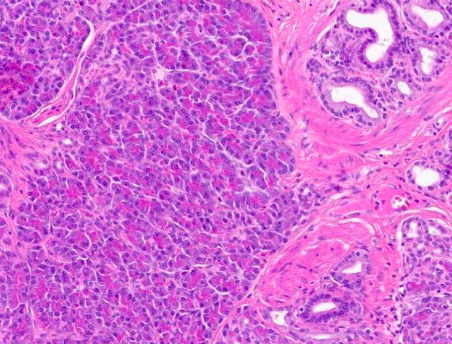

41세 여자가 정기검진 목적으로 위내시경을 시행받았다. 점막하종양이 의심되어 내시경적 절제술을 시행하였다. 조직검사 소견은 사진과 같다. 다음 중 해당하는 것은?

• 해당 조직사진의 우측에는 정상 위샘조직이, 좌측에는 pancreatic acinar cell들이 발견된다. Pancreatic acinar cell은 RNA content로 인해 basophilic한 가장자리와 zymogen granule (digestive enzyme)으로 인해 eosinophilic한 apex로 구분된다.

• 답은 3번 이소종(choristoma)이다.

• 이소종은 신체 내 비정상적인 위치에 존재하는 조직을 의미한다. 이때 발생한 조직은 조직학적 소견으로는 정상이며 덩이 내 배열 또한 질서적이다. 양성 종양과 유사하지만 종양보다는 congenital anomaly로 간주된다.

• 해당 소견을 과오종으로 생각할 수 있겠지만 위샘조직과 췌장 세포의 경계가 명확하며 췌장 세포의 조직학적 배열이 정상이기에 이소종으로 분류된다.